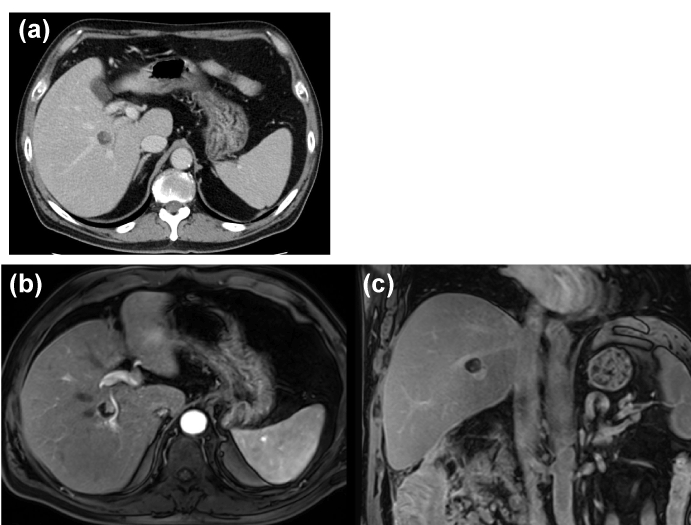

Colonoscopy showed chronic ascending colonic diverticulitis and no finding of malignancy. CT and magnetic resonance imaging (MRI) showed a gradually enhanced mural nodule in the cyst located at the proximal posterior segmental branch of the bile duct (Figure 1). T1-weighted MRI showed a low-intensity mass. The signals from the cystic lesion were high on T2-weighted images, except for the mural nodules. The cystic lesion was suspected to be a mucin-producing liver tumor, such as a mucinous cystic neoplasm of the liver, IPNB, a hemangioma, or a schwannoma of the liver.

Figure 1. Abdominal contrast computed tomography (CT) and enhanced magnetic resonance imaging (MRI) findings. (a) Contrast-enhanced CT shows a low-density hepatic lesion measuring 1.5 cm in diameter with mural nodules with contrast-enhanced high signals (a red arrow). (b, c) Contrast-enhanced MRI shows lesion with enhanced nodules located at the proximal part of the posterior bile duct.